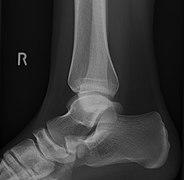

Radiological images